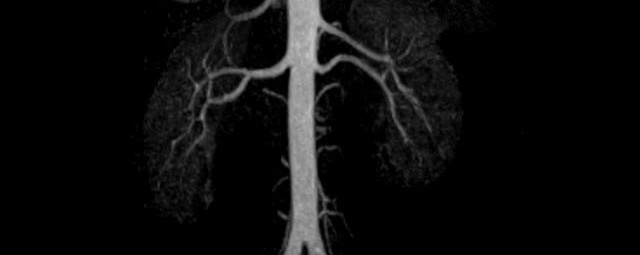

- Bauchgefäße

- Erfassung und Verlaufskontrolle bei arteriellen Aneurysmen (Aussackungen der Arterien), vor allem der Bauchaorta

- Darstellung von Gefäßengen an Nierenarterien, Baucharterien und Becken-/Beinarterien